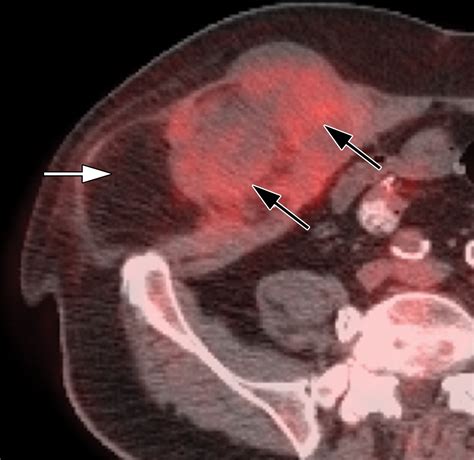

CT Scan High-resolution cross-sectional images to pinpoint the exact location and nature of the mass.

Because the abdomen contains a dense arrangement of structures, relying on a physical "self-exam" is rarely sufficient. A doctor will typically correlate physical findings with diagnostic imaging. For instance, an ultrasound might distinguish between a solid tumor and a fluid-filled cyst, while a CT scan provides the necessary detail to assess whether the mass in stomach involves surrounding blood vessels or lymph nodes. In some cases, a biopsy—the removal of a small tissue sample—is the only definitive way to characterize the cellular nature of the mass.